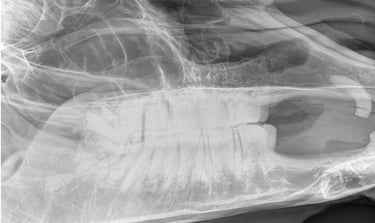

Is uw paard mank, hoefbevangen of is er een vermoeden van een halsprobleem? Dan kan het aangewezen zijn om een radiografisch onderzoek (RX) aan huis uit te voeren. Wij beschikken over een digitaal mobiel radiografietoestel, waardoor opnames eenvoudig bij u ter plaatse kunnen worden gemaakt.

Wij maken geen radiografische opnames in het kader van een radiografische keuring.

Dit onderzoek wordt uitgevoerd binnen een straal van 20 km rond de praktijk.